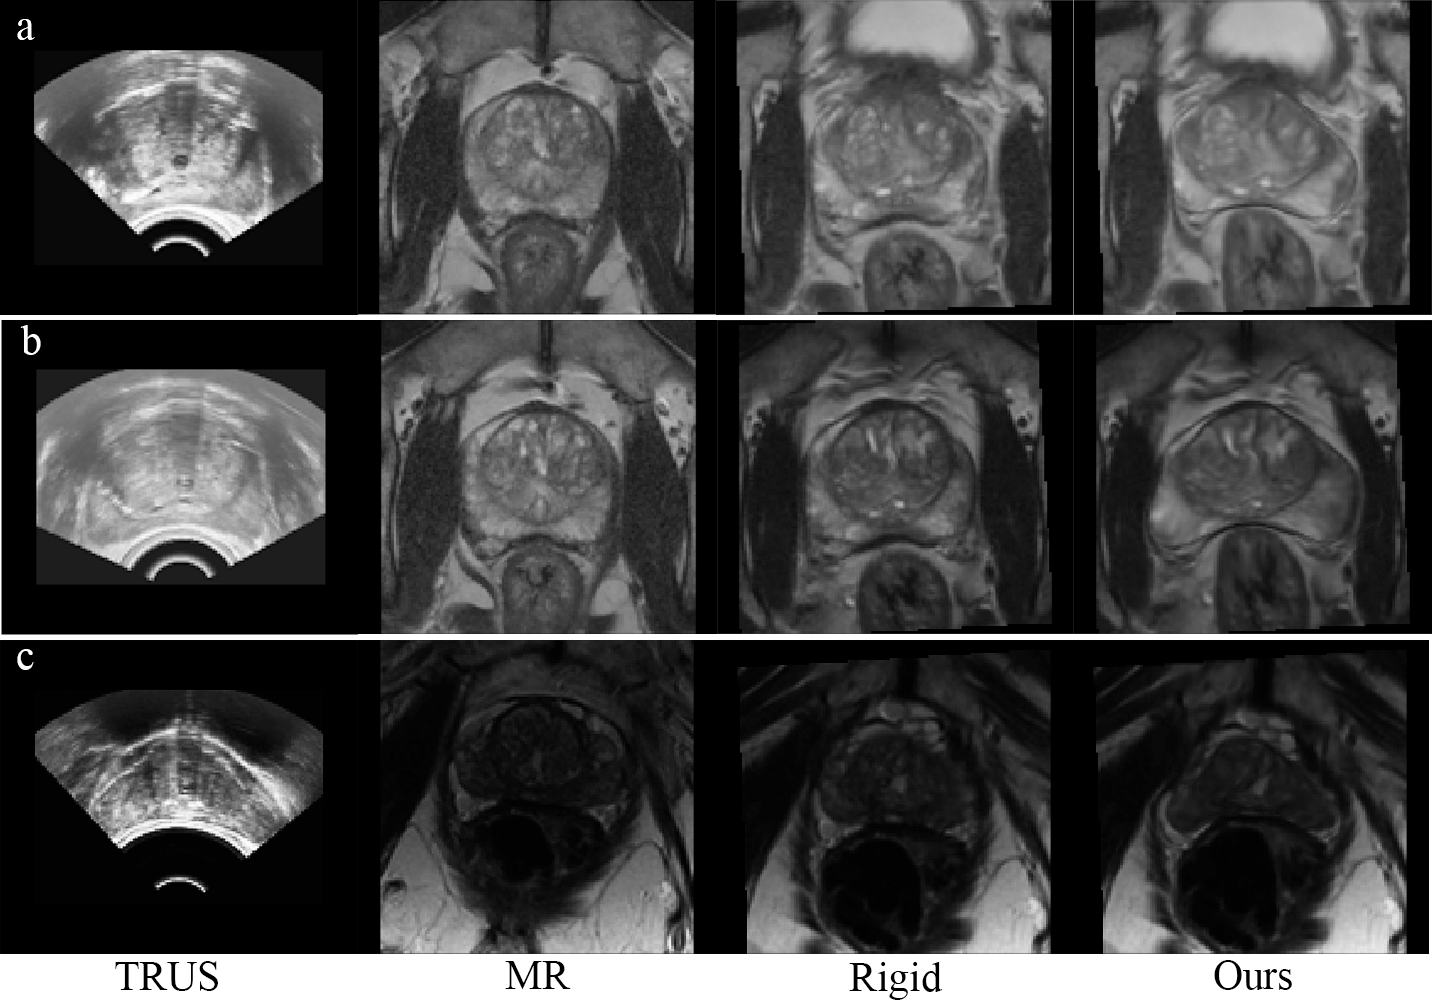

Table 1 reports the comparison results of different methods. The “Rigid” method refers to the rigid alignment in our approach. It can be observed that our registration method using all landmarks outperformed other methods in terms of DSC and TRE. Specifically, it surpassed [11] even with the same rigid alignment as initialization, highlighting the superiority of our registration architecture and salient region matching mechanism. Compared to [13], which excelled in surface registration, our method also attained better alignment on prostate surface and internal structures. Additionally, our method using only prostate mask also outcompeted [11, 13]. It had larger TRE compared to “Rigid+[11]” due to the lack of internal landmarks’ guidance. Fig. 4 shows some registration results. Our method effectively handled large and complicated deformations between MR and TRUS images.